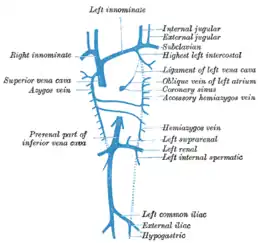

Anatomie de la veine cave supérieure

La veine cave supérieure est une veine courte du thorax (1 à 2 cm de long), mais large, qui draine le sang de la tête, des membres supérieurs et du haut du thorax vers le cœur. Elle naît de la rencontre des deux veines brachiocéphaliques au sommet du thorax, et la veine azygos la rejoint peu avant le cœur à sa face postérieur. Elle est située à la droite et à la partie antérieur du médiastin, au contact du poumon droit.